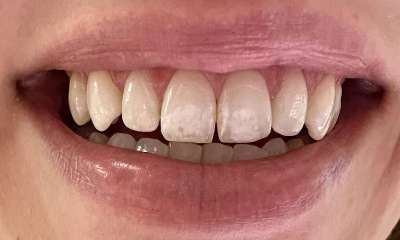

Crowned 10 teeth on the upper arch to transform the patient's smile and achieve their cosmetic goals!